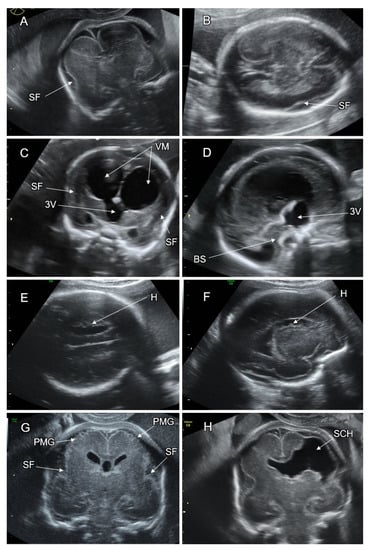

6.3.1. Polymicrogyria

6.3.2. PMG Associated with Schizencephaly